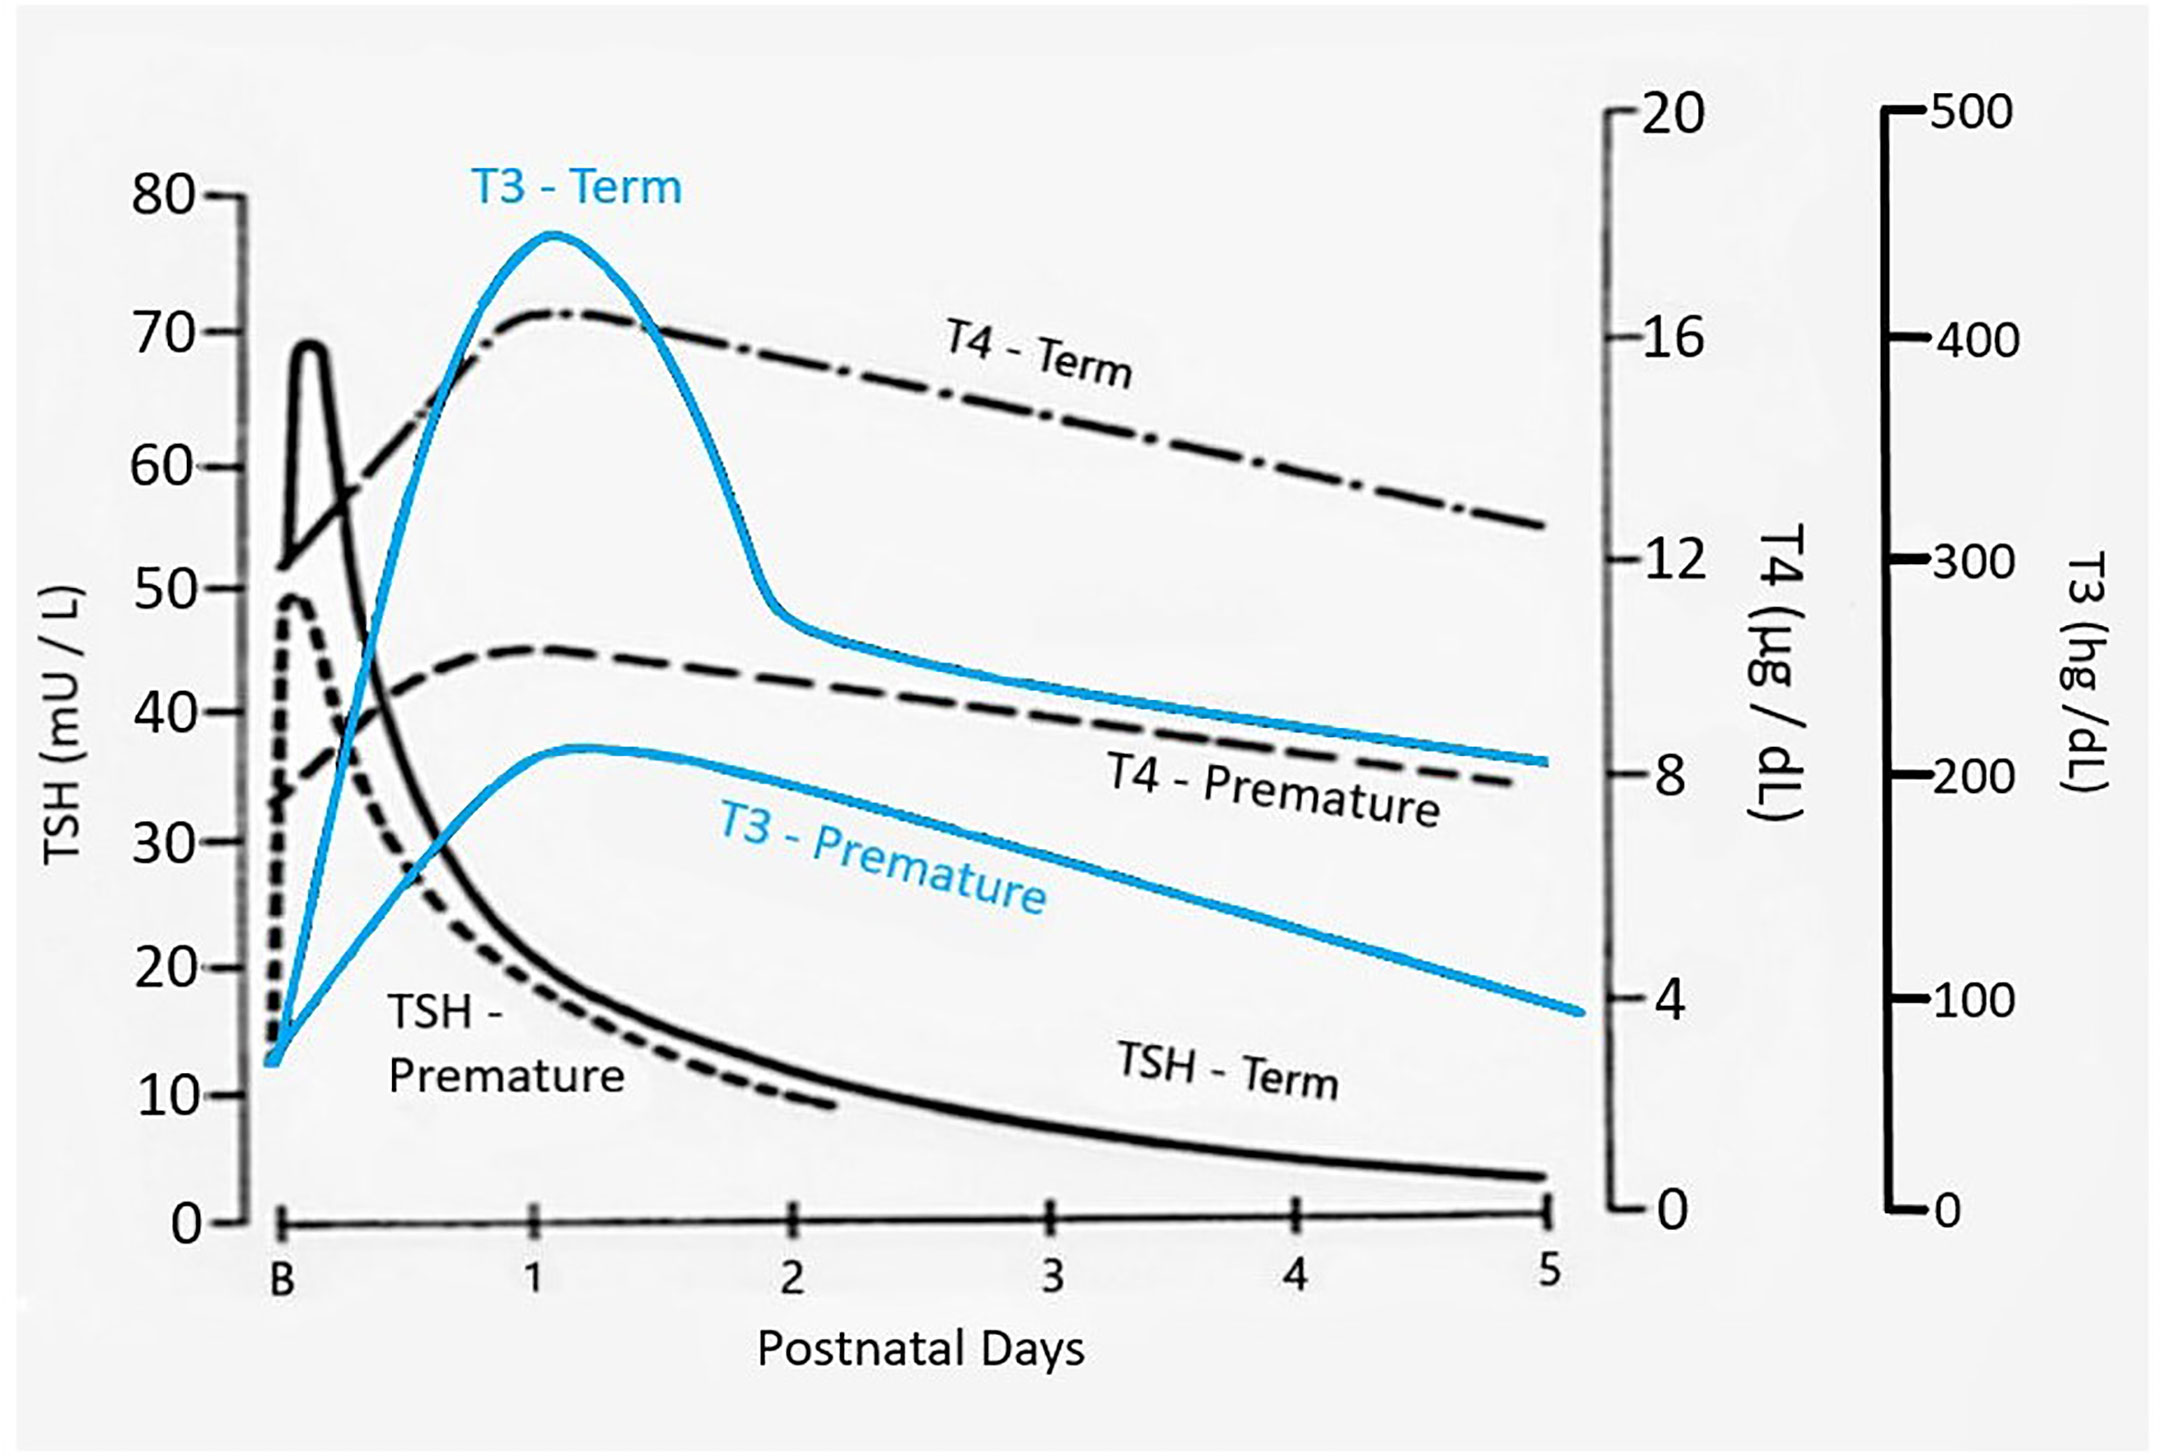

Frontiers Thyroid Function In Preterm Low Birth Weight Infants Impact On Diagnosis And Management Of Thyroid Dysfunction